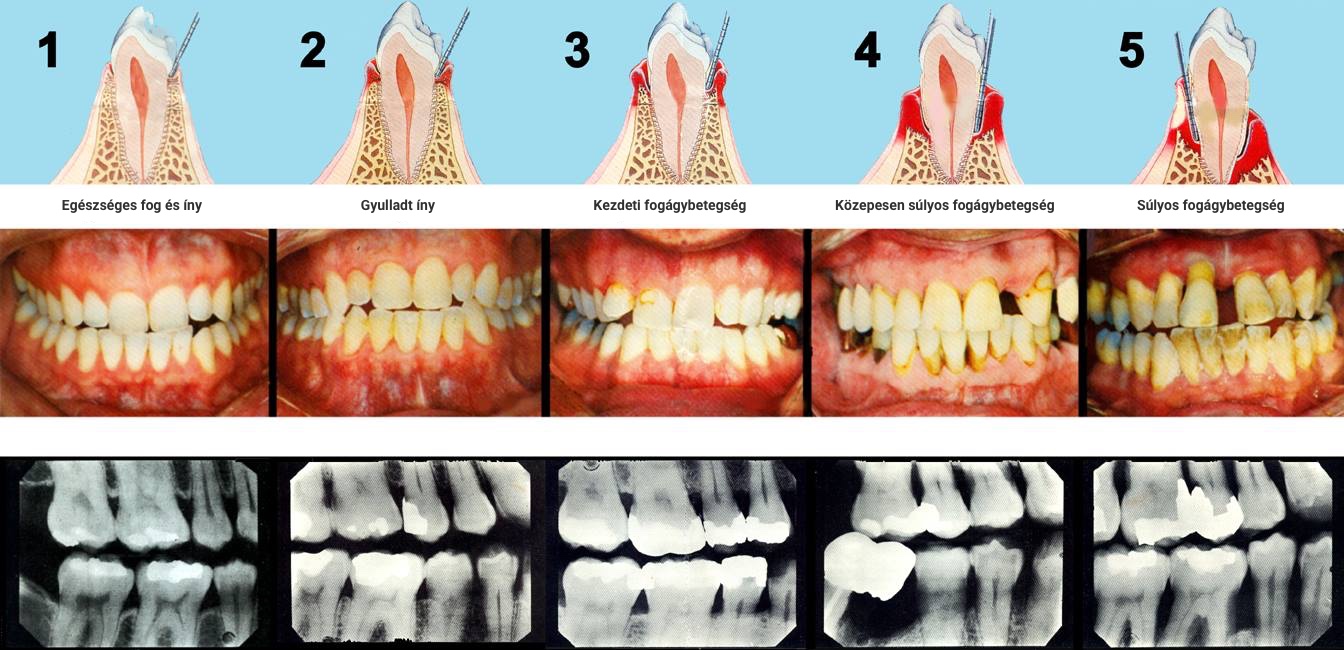

Íny és fogágybetegség kezelése

A fogágybetegségben szenvedő páciensek kezelése összetett feladat. Az első találkozás alkalmával betegség súlyosságát, a talált elváltozás esetleges okait vizsgáljuk meg. Számos esetben a páciensek a betegség előrehaladott stádiumában kerülnek szakemberhez, ezért a fogágy tisztítását megelőzően, vagy azzal egy időben szükségessé válhat a már reménytelen fogak eltávolítása. Ilyen esetekben ideiglenes pótlással állítjuk helyre az esztétikát és rágófunkciót.

JELLEMZŐ PANASZOK

• ínyvérzés,

• ínyduzzanat

• fogmozgathatóság,

• szájszag,

• fogközök résessé válása.

A szájüregi tüneteken túl, a fogágybetegség hatással van a szervezet más területeire is. Ma már több klinikai tanulmány kimutatta hogy a fogágybetegség fontos szerepet játszik a miokardiális infarktus kialakulásában, cukorbetegségben, valamint alacsony születési súlyt, és koraszülést eredményezhet.